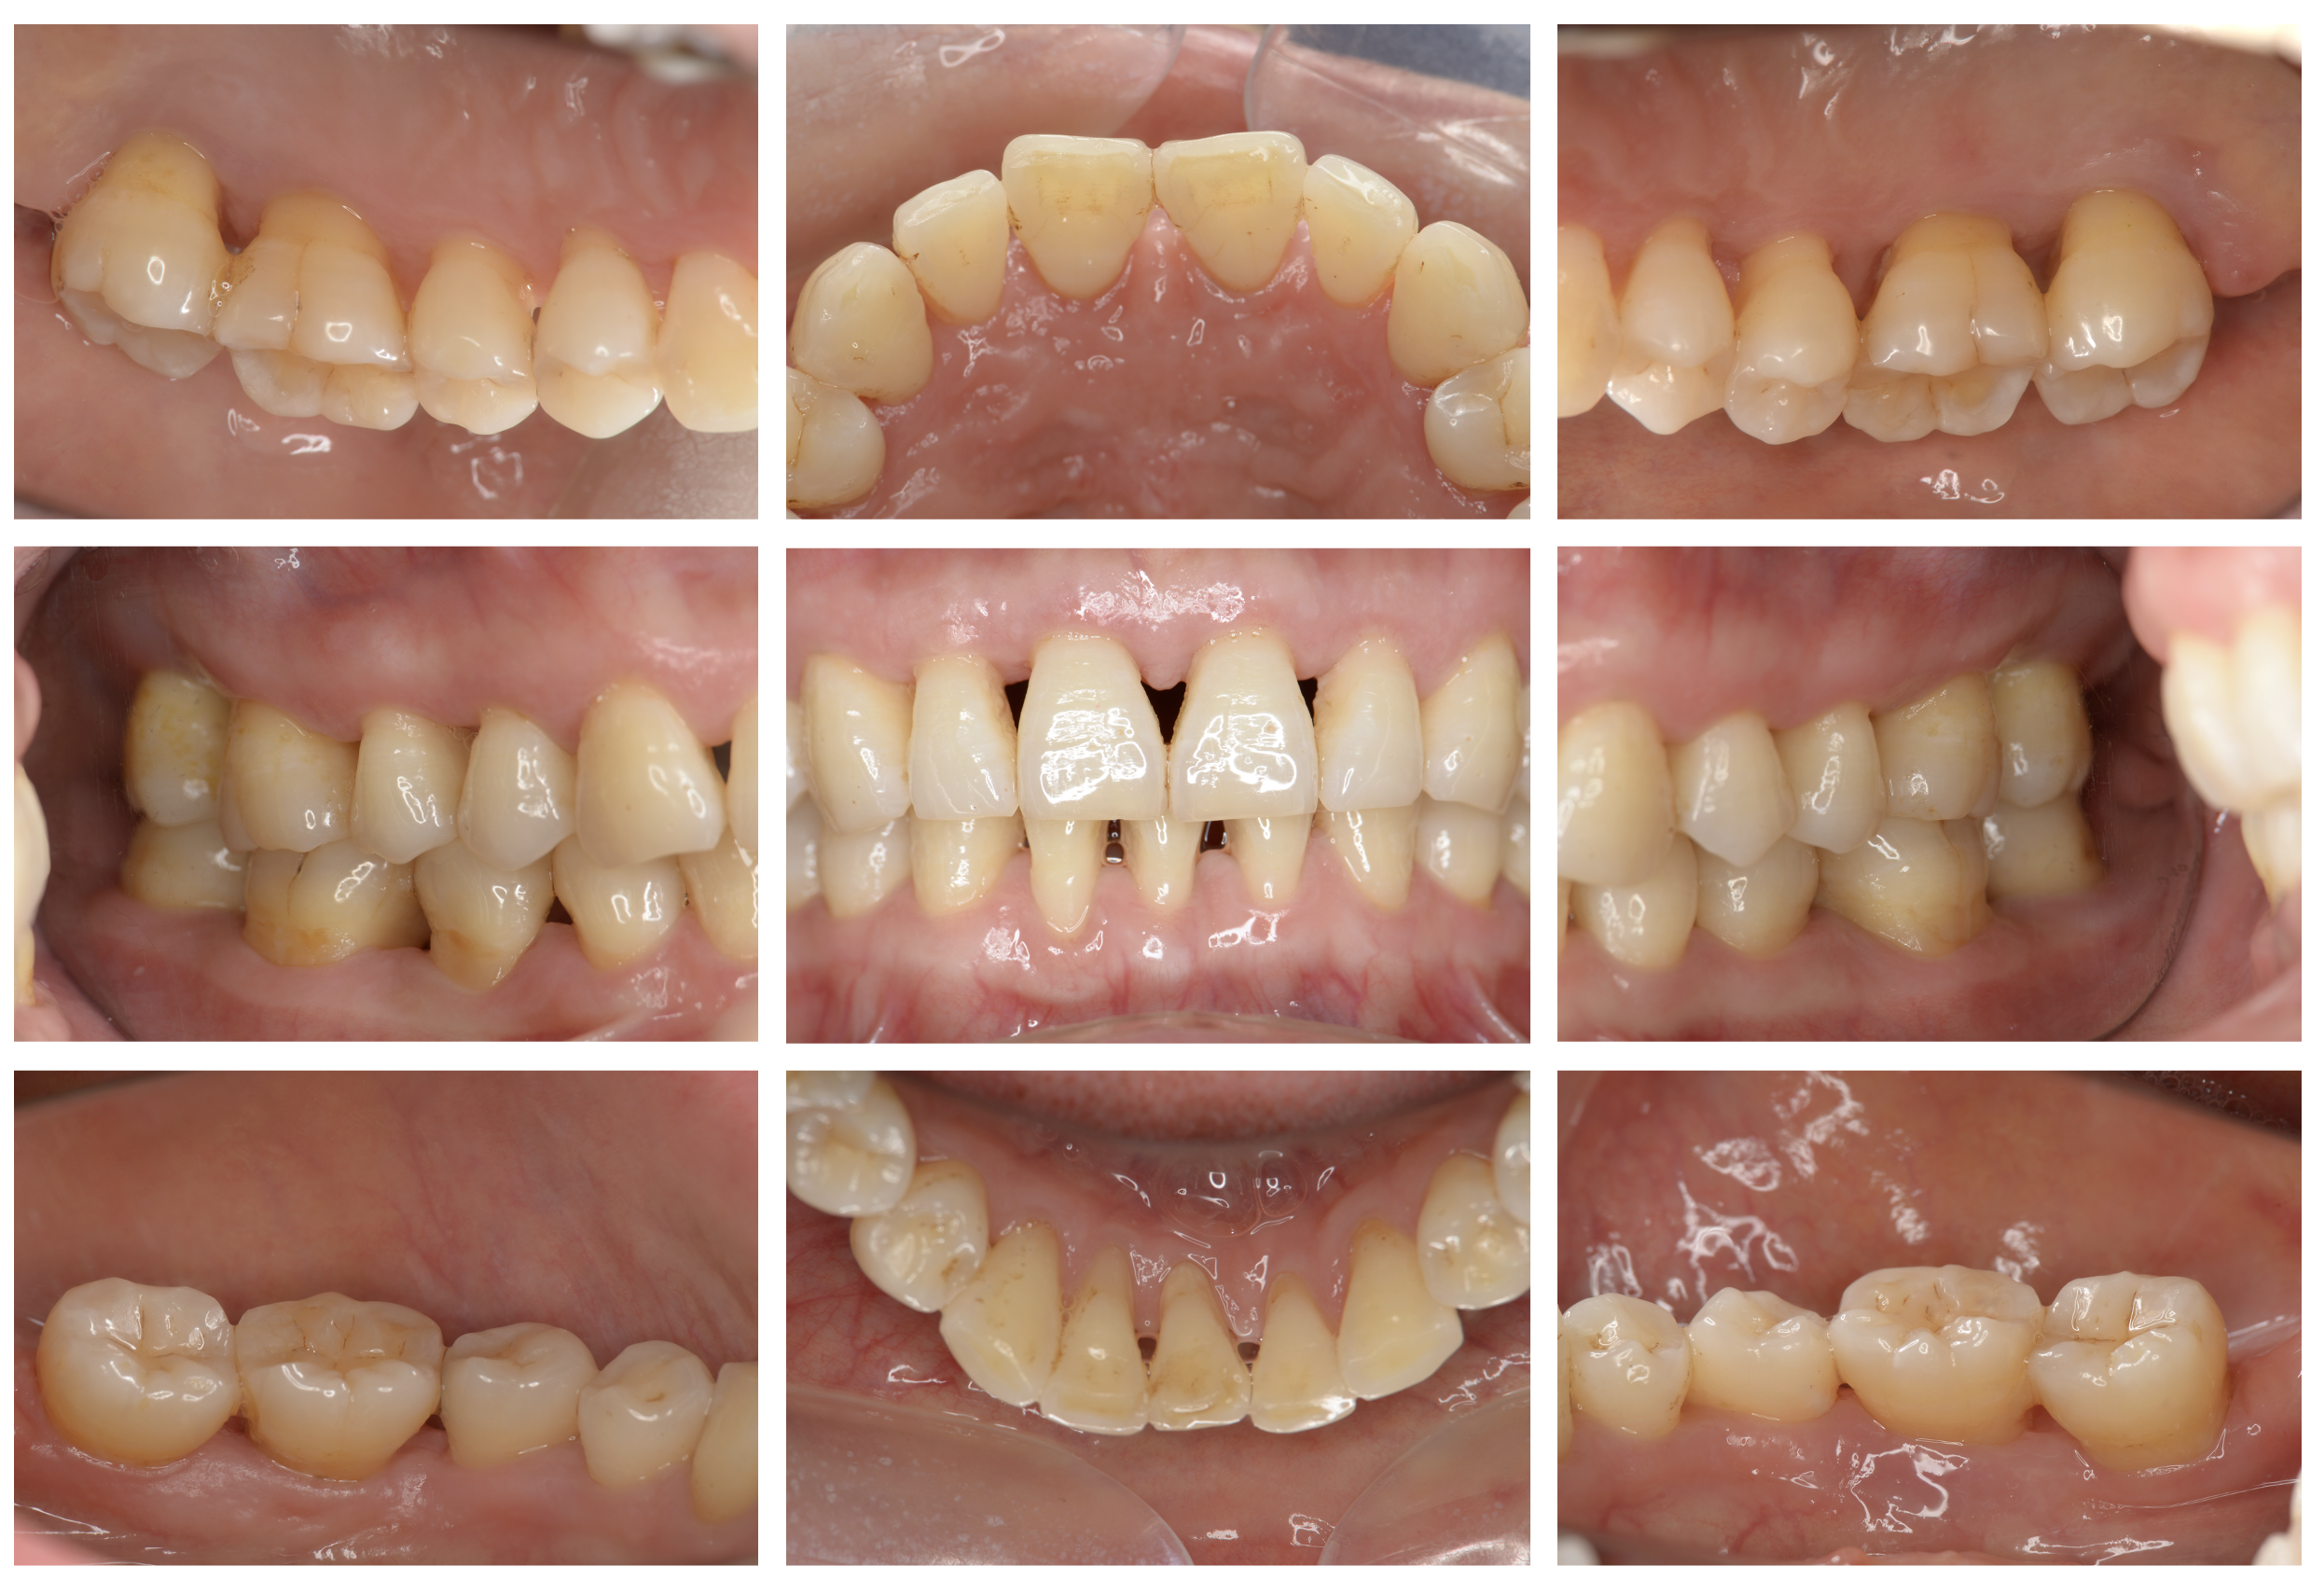

症例 06

下がった歯茎を元通りにしたい

術前

術後5年

| 主訴 | 歯茎が下がってきている。 歯磨きもしにくいし、見た目も気になる。 このまま下がって歯が抜けないか心配。 |

|---|---|

| 治療内容 | ブラッシング指導、歯石の除去 歯周形成手術(結合組織移植術) →歯茎の再生手術 |

| 治療期間 | 2ヶ月 術後3ヶ月経過してメインテナンスに移行 |

| 費用 | 77,000 *対象歯の本数により異なります。 |

| リスク・副作用 | 手術部位が2箇所になります。移植片を採取する部位(上あごの歯肉)と移植する部位(歯肉退縮部位)。特に採取部位では疼痛や出血を伴います。また、退縮量が大きい場合や症例によっては2度に分けて手術を行う場合があります。 |